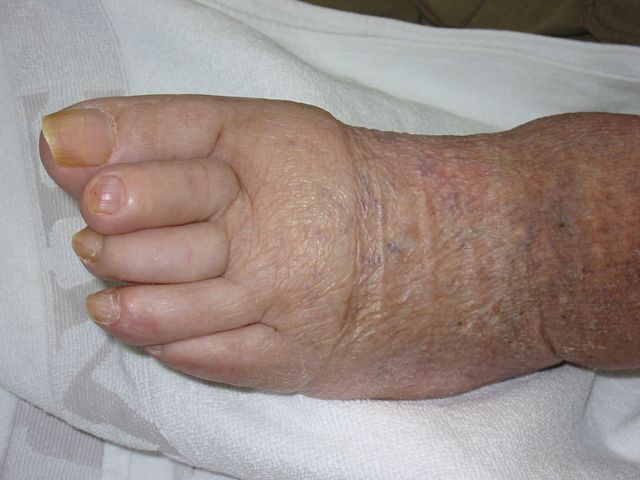

Necrosis periférica en pie diabético.